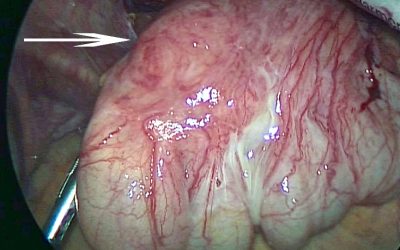

Un particolare caso di ernia interna del cieco

di Enrico Ganz Si definisce “ernia interna” l’impegno, ovvero la protrusione, di un viscere in una lacuna congenita o post-traumatica di un meso, oppure in un recesso del cavo peritoneale (19). Usualmente questi recessi sono fisiologici, quale è la borsa...